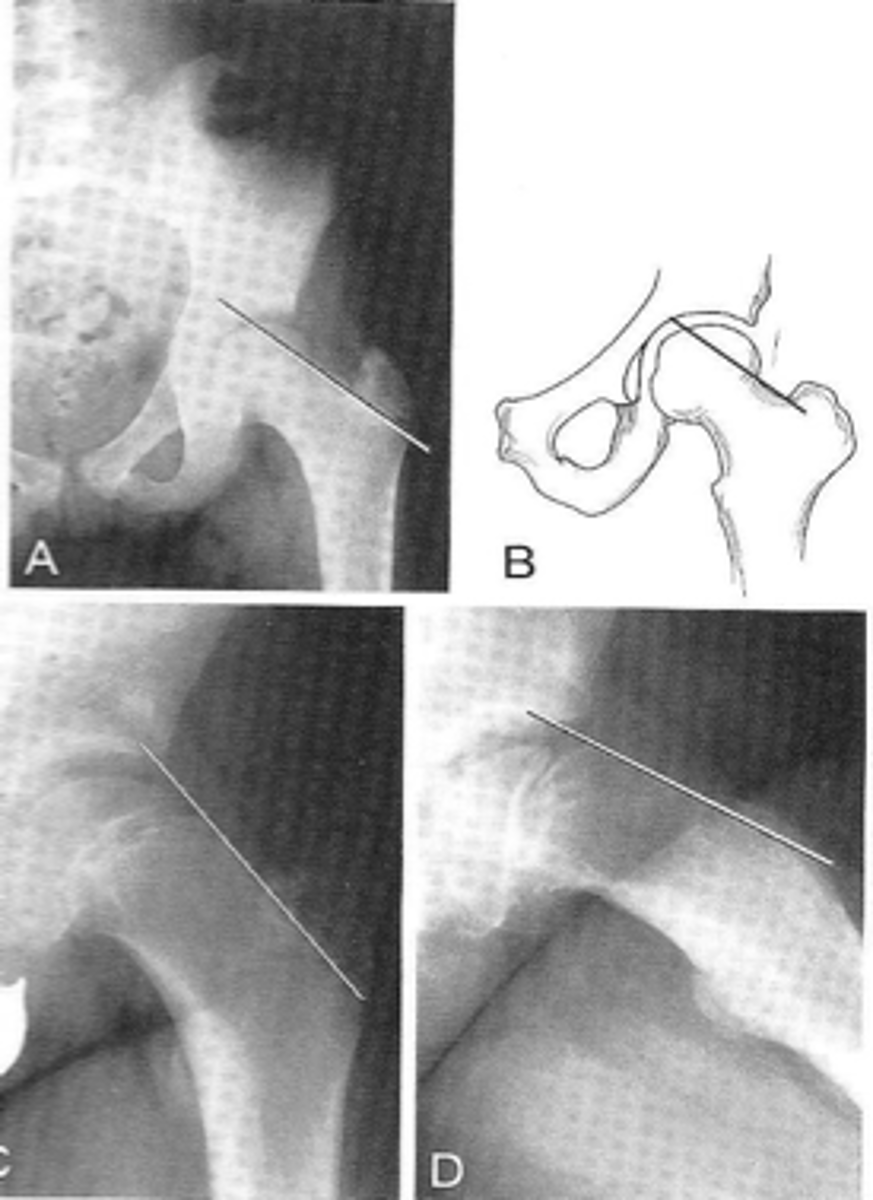

Shenton's line

- AP hip

- AP pelvis

- Smooth arc along femoral neck

- Obturator foramen

Shenton's line landmarks

Continuous and smooth

- Hip dislocation

- Femoral neck fracture

- Slipped epiphysis

Clinical significance of Shenton's line

<p>Clinical significance of Shenton's line</p>